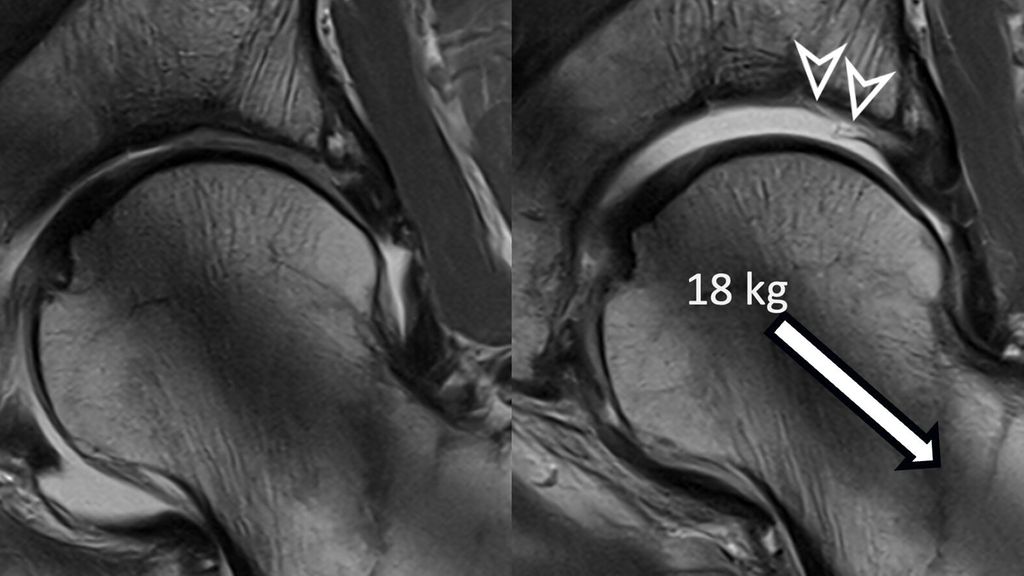

To improve visualization of the central joint cavity during MR arthrography, axial leg traction can be applied, similar to the joint distraction needed during hip arthroscopy (Fig. 1). Traction MR arthrography of the hip has shown high accuracy in detecting chondrolabral lesions, ligamentum teres injuries, and intra-articular loose bodies and has demonstrated its value in predicting failure of FAI surgery.5–8 It is particularly helpful for better visualizing the extent of cartilage damage in older patients with mild radiographic joint degeneration and thus aid in surgical decision making. Traction MR arthrography can also detect unstable labral tears in patients with hip dysplasia and may aid in planning treatment for femoral head necrosis in young patients with early collapse and preserved joint space.4